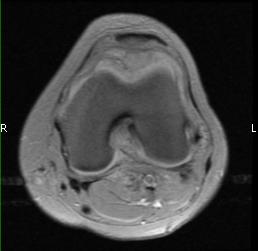

MRI (Fig. 1-10)

- Periarticular or synovial nodular mass with varying degrees of bone erosion.

- Nodular lesion with areas of hemosiderin (low signal on all sequences) and hemorrhage.

- On fat suppress images the tumor is high signal and hemosiderine cannot be seen.

- Joint effusions and bony erosions are well demonstrated. As with CT, contrast enhancement is typical.

Fig. 1-10: Magnetic Resonance of a PVNS of the knee shows a synovial mass with minimal bone erosion of the medial articular plate. On T1W and T2W images shows a tumor with low intensity areas (hemosiderin) and hemorrhage. Joint effusion is well demonstrated. Post contrast images demonstrate an irregular pattern of enhancement.